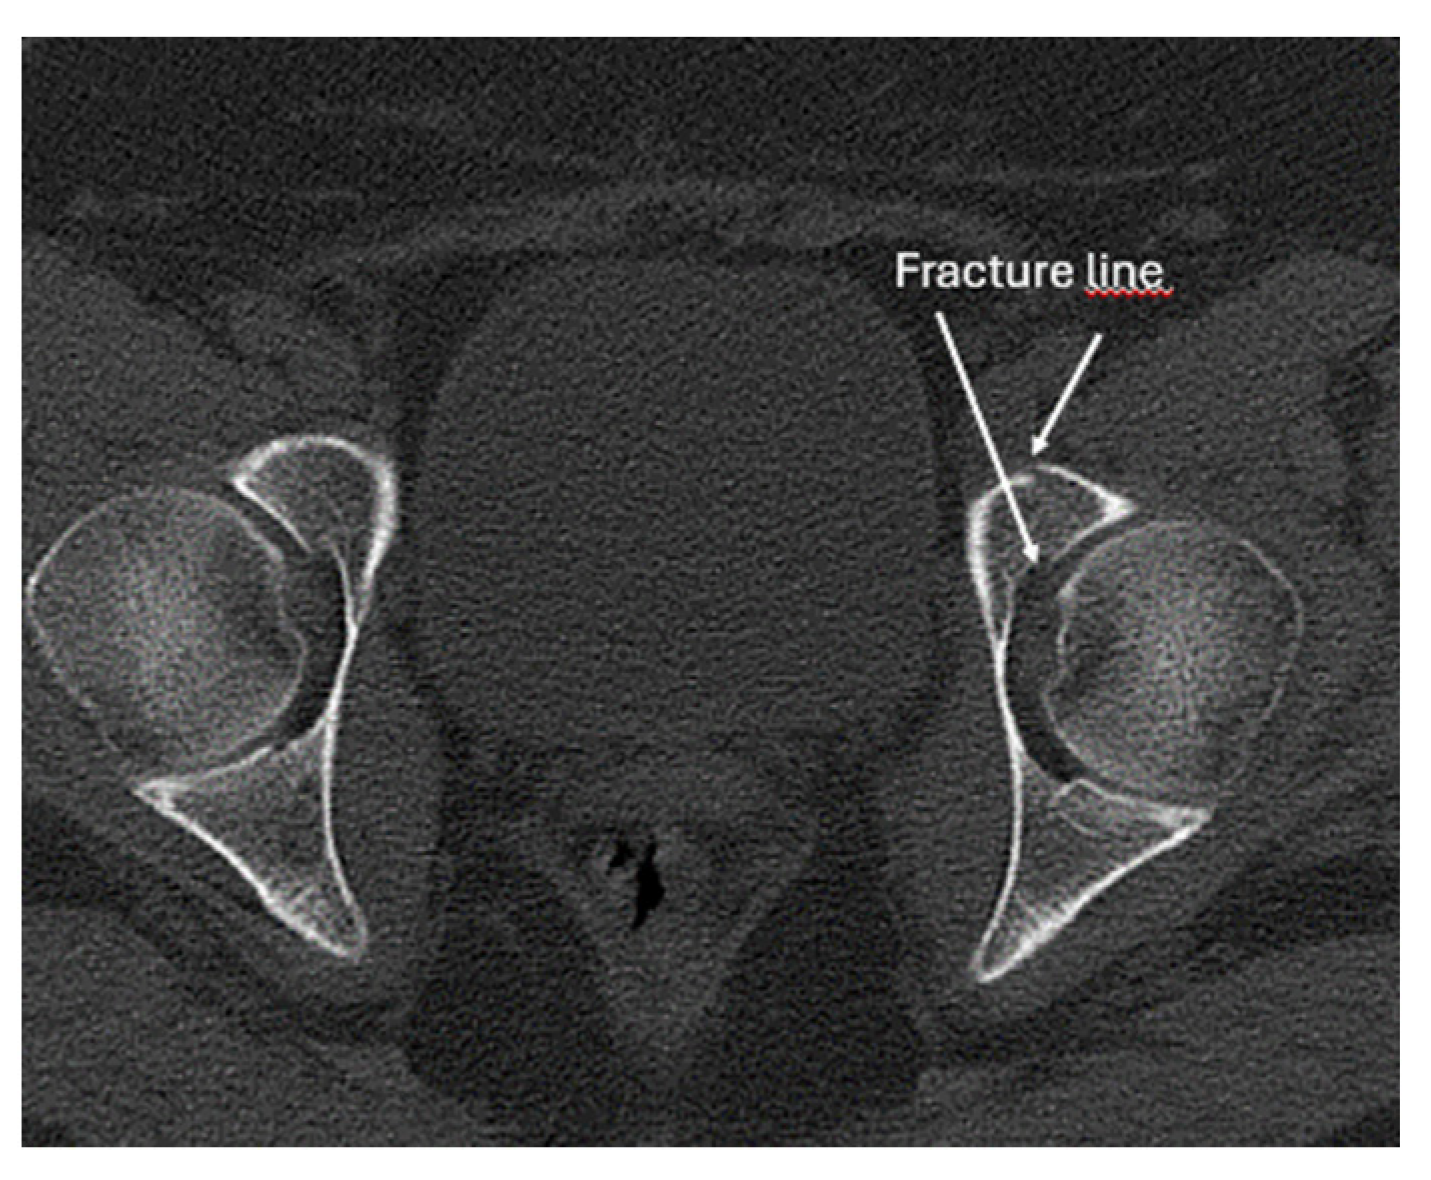

- Irregularity, interruption, or gaps in the cortical line: the cortical bone normally appears as a continuous, bright echogenic line, which is interrupted or irregular in the presence of a fracture.

- Bulging or abnormal angulation of the cortical layer: deformities or outpouchings of the normally straight cortical surface indicate displacement or bending at the fracture site.

- Dislocation: misalignment of bone fragments, visible as separation or shift from their normal anatomical position.

- Angulation: an abnormal angle formed between fracture fragments, indicating malalignment.

- Not suitable for all types of fractures: intra-articular fractures often need complimentary imaging: X-ray and/or CT.